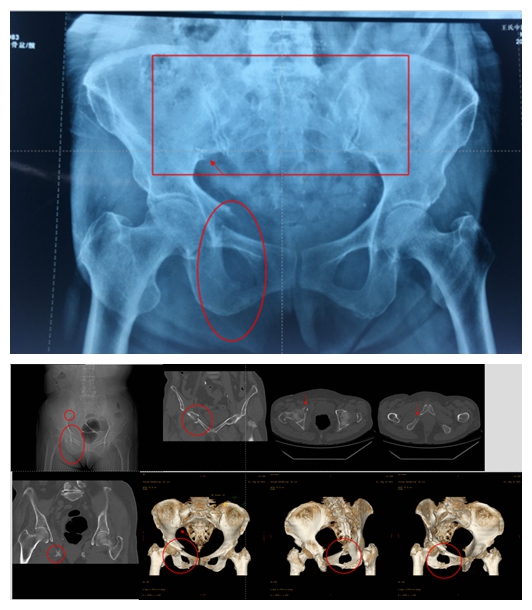

例1:

◆术前影像学资料

麻醉成功后,术中经过骨折的复位,在机器人导航下经皮成功置入螺钉固定,病人体表只有2厘米左右的手术切口。

◆术中